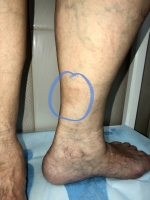

Панникулит Есть еще одно заболевание, которое похоже на склеродермию по кожным проявлениям. Это панникулит, или болезнь Вебера-Крисчена. Основным проявлением являются узлы в подкожной клетчатке с гиперемией кожи над ними. Кроме местной бляшечной формы, болезнь может иметь и системные проявления, в виде поражения внутренних органов. На самом деле диагностика этой болезни сложна, ибо у неё нет четких критериев. На фото 3 так выглядят узлы при узловатой эритеме. На фото 4 мое наблюдение узловатой эритемы у пожилой пациентки.

Узловатая эритема и варикоз

Узловатая эритема Часто возникает при сенсибилизации организма или после перенесенной инфекции. Проявляется в виде подкожных уплотнений с краснотой кожи. Может длиться около месяца, сопутствуя многим системным болезням. Узлы вначале болезненные. Часто появляются боли в суставах. Ну а к флебологу такие пациенты приходят потому, что узлы чаще на ногах и в зоне частых трофических нарушений - передняя и внутренняя поверхность голени. Можно ошибочно принять как индурацию кожи на фоне венозной недостаточности, особенно если есть варикозные вены. На втором снимке моя пожилая пациентка с венозной недостаточностью.